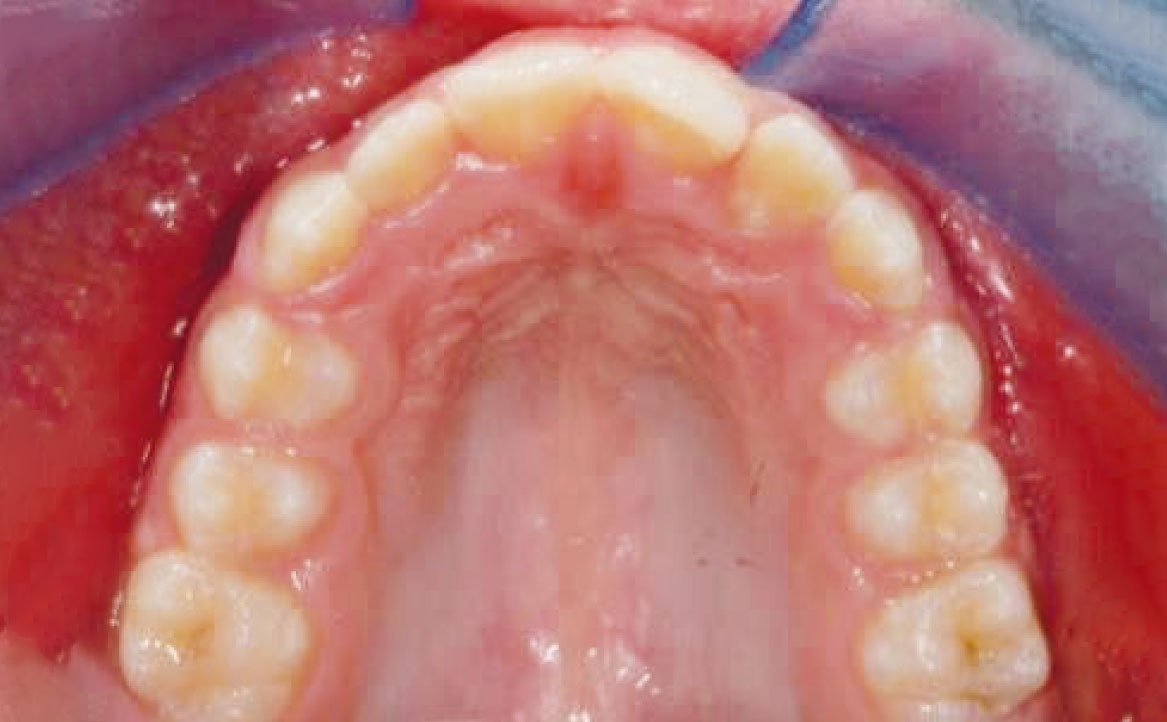

Viene eseguita la consueta raccolta dei records: fotografie intra ed extra orali, modelli e indagini radiografiche di primo livello (OPT e teleradiografia latero-laterale) (fig. 2-11).

Al fine di risolvere la contrazione dell’arcata mascellare sul piano trasverso è stato applicato un disgiuntore rapido ancorandolo ai denti decidui ed estendendo i bracci palatali saldati agli elementi 53 e 63. Mentre, per la risoluzione della carenza mandibolare è stato pianificato l’utilizzo del Twin Block.

La prima fase di trattamento ha previsto l’applicazione di un espansore palatale per dodici mesi. Tale dispositivo, applicando una pressione controllata sulla regione palatale, ha permesso di ottenere l’espansione dell’arcata superiore. Questa prima fase terapeutica ha consentito di preparare l’arcata superiore ad accogliere l’arcata inferiore durante la correzione ortopedica della retrusione mandibolare e della micro-mandibolia mediante Twin Block.